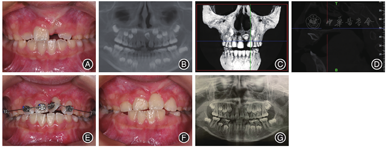

方移动;I:上颌改良Nance托;J:治疗后口内像;K:治疗后全颌曲面断层片;L:治疗后头颅侧位片病例3男,8岁3个月,以"左侧中切牙未萌,要求检查"为主诉就诊。临床检查:替牙列,11、12、22已萌,21未萌,11、22向缺隙处倾斜、缺牙间隙变小、上中线左偏,前牙浅覆

浅覆盖,双侧第一磨牙中性关系。X线片及CBCT示:11已萌出,牙根发育至根尖1/3,21唇侧倒置埋伏牙,牙根未发育完成,根尖孔未闭合,冠根比约为1∶1,牙根弯曲部分在根尖1/3,弯曲度约为30°。矫治过程:采用外科开窗联合正畸牵引进行治疗。使用改良Nance托加强支抗,注意牵引过程中的牵引方向,牵引力均控制在60 g以下,每2 ~ 3周复诊加力。约5个月牙齿唇倾度基本正常,粘接托槽,置推簧扩大21间隙后按顺序依次使用0.012 NT、0.016 NT、0.016 × 0.016 NT、0.018 × 0.022 NT排齐牙齿。矫治时长为8个月,矫治后前牙浅覆

浅覆盖,嘱定期复查,采用Hawleys改良保持器进行保持(图3)。